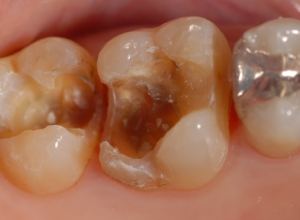

治療前の状態です。金属の詰め物が入っています。

金属を除去すると茶色の虫歯があるのがわかります。